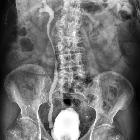

pathologisches MCU (Miktionszysturethrogramm). Das über die Harnblase applizierte Kontrastmittel dringt bereits ohne Miktion bis in die Uretheren ein und füllt beide (konsekutiv dilatierte) Nierenbecken.Technik: Die Bilder wurden mit 0,1 mm Cu-Filter, gepulster Durchleuchtung und last image hold erzeugt, sodass nur eine sehr geringe und keine unnötige Strahlenbelastung nötig war.

Vesicoureteric reflux (VUR) grading divides vesicoureteric reflux according to the height of reflux up the ureters and degree of dilatation of the ureters:

- grade 1: reflux limited to the ureter

- grade 2: reflux up to the renal pelvis

- grade 3: mild dilatation of ureter and pelvicalyceal system

- grade 4

- tortuous ureter with moderate dilatation

- blunting of fornices but preserved papillary impressions

- grade 5

- tortuous ureter with severe dilatation of ureter and pelvicalyceal system

- loss of fornices and papillary impressions

It is important to note that each side may have a different grade of reflux.